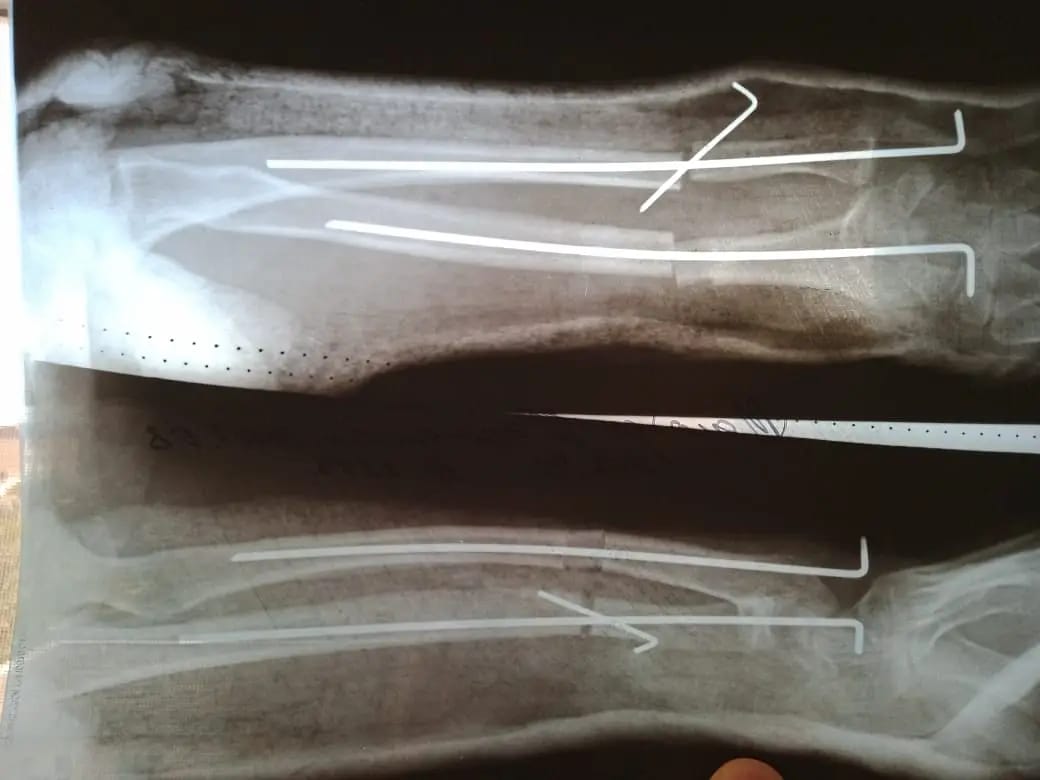

ناۋقاس وسىدان بىرنەشە جىل بۇرىن قولىن اۋىر جاراقاتتاپ, شىنتاق سۇيەگى ءوسىپ, كارى (لۋچەۆايا) سۇيەگى وسپەي قالعان. سالدارىنان قولىنداعى سۇيەكتەرى قيسايىپ, وزدىگىنەن قيمىل جاساۋعا كەدەرگى كەلتىرگەن.

«وتا جاسالعان ناۋقاس ءۇش اي بۇرىن قالالىق كلينيكالىق بالالار اۋرۋحاناسىنا كەڭەس الۋعا كەلگەن بولاتىن. تەكسەرە كەلە ناۋقاستا جاراقاتتىڭ سالدارىنان سۇيەگى قيسايعانى انىقتالدى. وپەراتسيانى بىردەن جاسامادىق. سەبەبى مۇنداي وتا بالانىڭ سۇيەك ءوسۋى توقتاۋعا جاقىنداعان كەزدە جاسالادى. وپەراتسيا كەزىندە قاتتى ءوسىپ كەتكەن سۇيەكتى قىسقارتىپ, وسپەي قالعان سۇيەككە جالعاپ, ارنايى قۇرىلعىمەن بەكىتىپ بەردىك. مۇنداي وتانى ءبىرىنشى رەت جاسادىق. وسىعان دەيىن سۇيەگى قيسىق وسكەن ناۋقاستارعا وتا جاساۋ ءۇشىن نۇر-سۇلتان قالاسىنداعى ەمدەۋ مەكەمەلەرىنە جولداما ارقىلى جىبەرەتىنبىز. ەندى مىنە مۇنداي وتانى ءوزىمىز جاساۋعا دايىنبىز» دەيدى ورتوپەد-تراۆماتولوگ باعجان تۇردىقۇلوۆ.